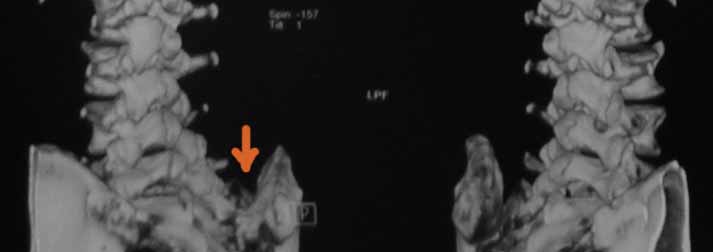

В 2009г установлен диагноз - сакроилеит справа.На представленных КТ имеется гипертрофия заднего отдела правой подвздошной кости с образованием контакта с задней поверхностью крестца.В январе 2011 года выполнена попытка удаления гипертрофированного участка подвздошной кости. удаленные участки кости исследованы гистологически - губчатая кость с элементами гиалинового хряща. После операции положительного эффекта не получено. На контрольной КТ от 04.2011 обнаружено что, желаемого результата операции не получено(интересующий участок удален частично), при этом имеется расслоение заднего отдела правой подвздошной кости.

На первичных КТ от 19-12-2009 определяется частичное анкилозирование правого крестцово-подвздошного сочленения, а на последних, от 11-04-2011 протяженность анкилозированной зоны значительно больше - сакроилеит прогрессирует, (с левой стороны вроде тоже признаки сакроилеита появились - не очень понятно из-за качества снимка). Значимых дуральных и радикулярных конфликтов действительно нет. "расслоение кости" - рентгенологически выглядит как травматический перелом подвздошной кости. Что делать? - наверное, искать серонегативные спондилоартропатии у ревматолога.